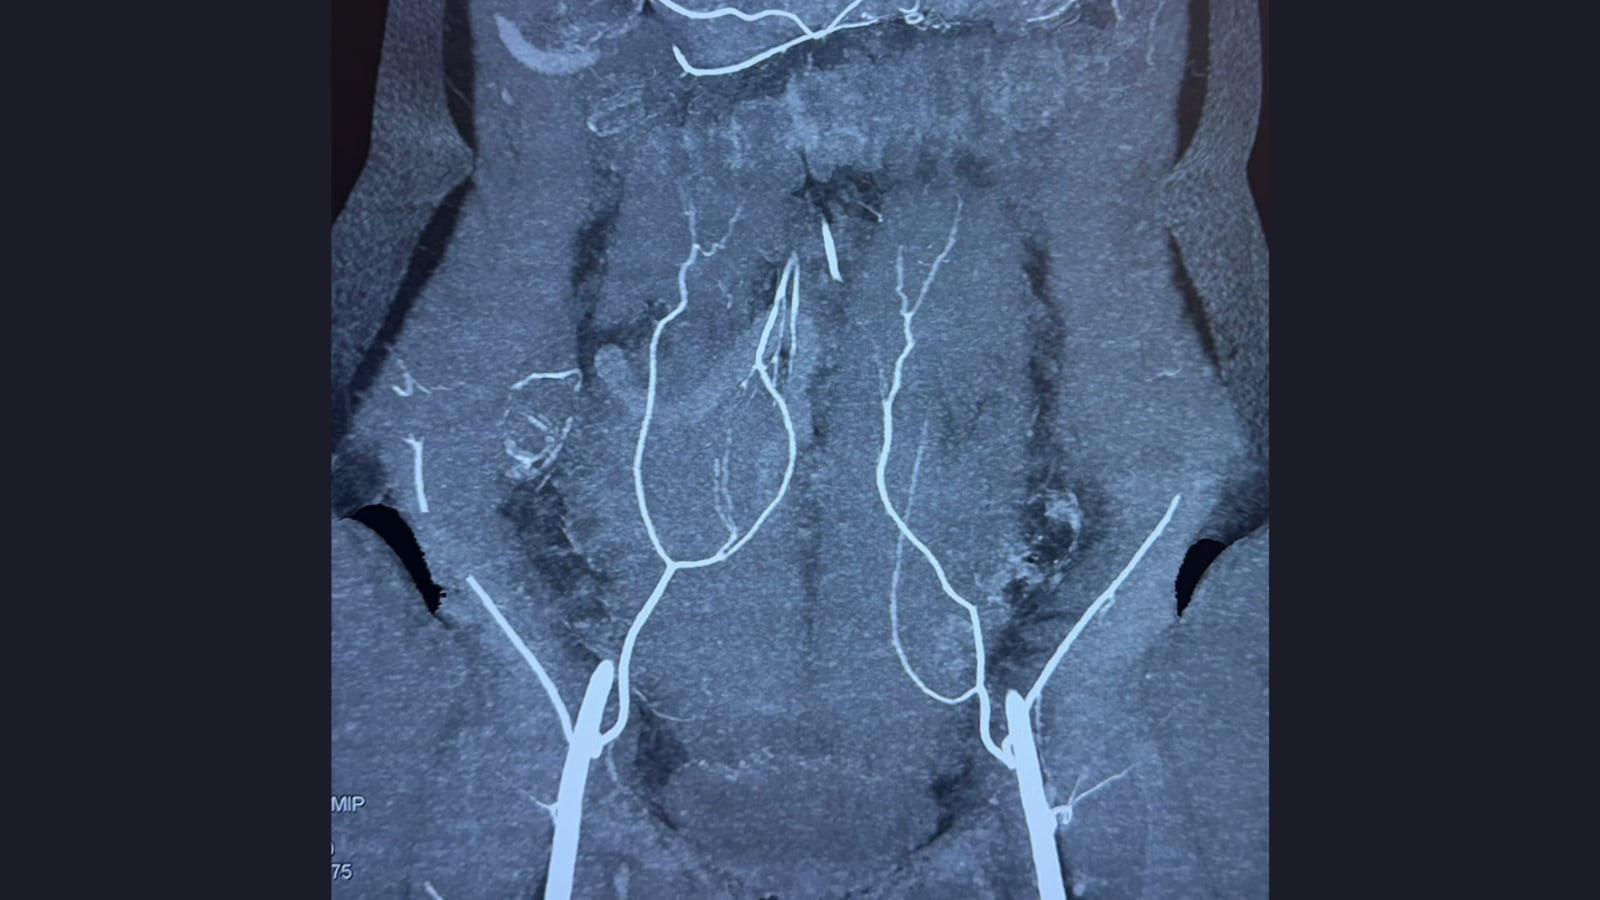

Breast reconstruction is a surgical procedure carried out after a mastectomy to recreate the shape and appearance of a breast. The aim is to restore body balance and help individuals feel more comfortable with their physical appearance following breast removal. The reconstructed breast can be created either with a medical implant or by using tissue taken from another area of the body such as the abdomen, back or thighs.

Autologous (Flap) Reconstruction

This technique uses the patient’s own tissue, which may include skin, fat and sometimes muscle, taken from another part of the body. Common donor sites include the abdomen, back or thighs. Flap reconstruction typically creates a breast that looks and feels more natural and adjusts with body changes over time. However, it is usually a longer and more complex surgery with a slightly extended recovery period.

Among advanced techniques, the DIEP (Deep Inferior Epigastric Perforator) flap has gained increasing attention. The procedure uses skin and fat from the lower abdomen while preserving abdominal muscles, helping maintain core strength and reducing the risk of long-term weakness.

“Because the tissue is living and well vascularised, the reconstructed breast integrates naturally with the body and settles over time,” Dr Gupta explains. “For most patients, it becomes a one-time, definitive reconstruction.”